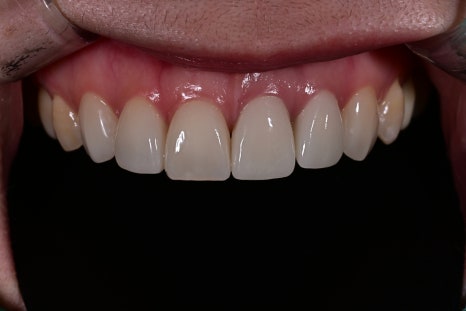

Comparison before and after treatment

<BEFORE>

<AFTER>

The patient first mentioned the naturalness of the color.

The existing crown had a noticeable brightness difference compared with the surrounding teeth,

which she described as looking like an “overlay,”

but the newly designed OBZERO looked natural even without makeup,

and she said it felt like her own teeth.

In addition, the incisal edge gained natural translucency and volume,

and the harmony with the lip line when smiling improved significantly.

She also said it looked more natural in photos.